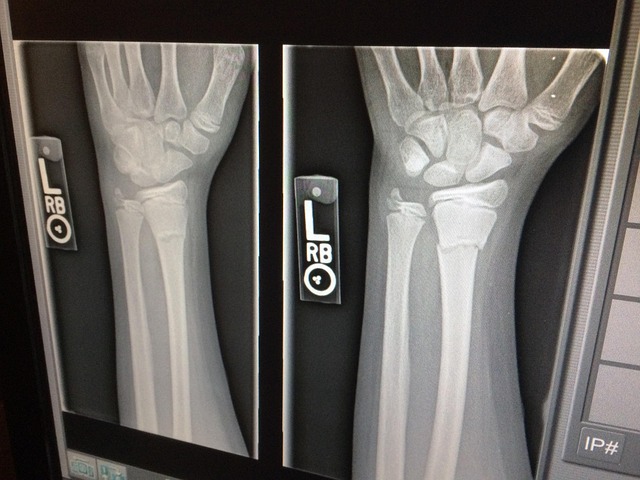

En septiembre de 2025, el Ministerio de Salud y Protección Social expidió la Resolución 1811 de 2025, una norma que moderniza y regula el uso de equipos generadores de radiación ionizante, la prestación de servicios de protección radiológica y el control de calidad en prácticas médicas, veterinarias, industriales e investigativas .

- Licencias de práctica médica, veterinaria, industrial o de investigación con equipos de rayos X u otros generadores de radiación.

- Categorización de prácticas médicas (I, II, III) según nivel de riesgo .